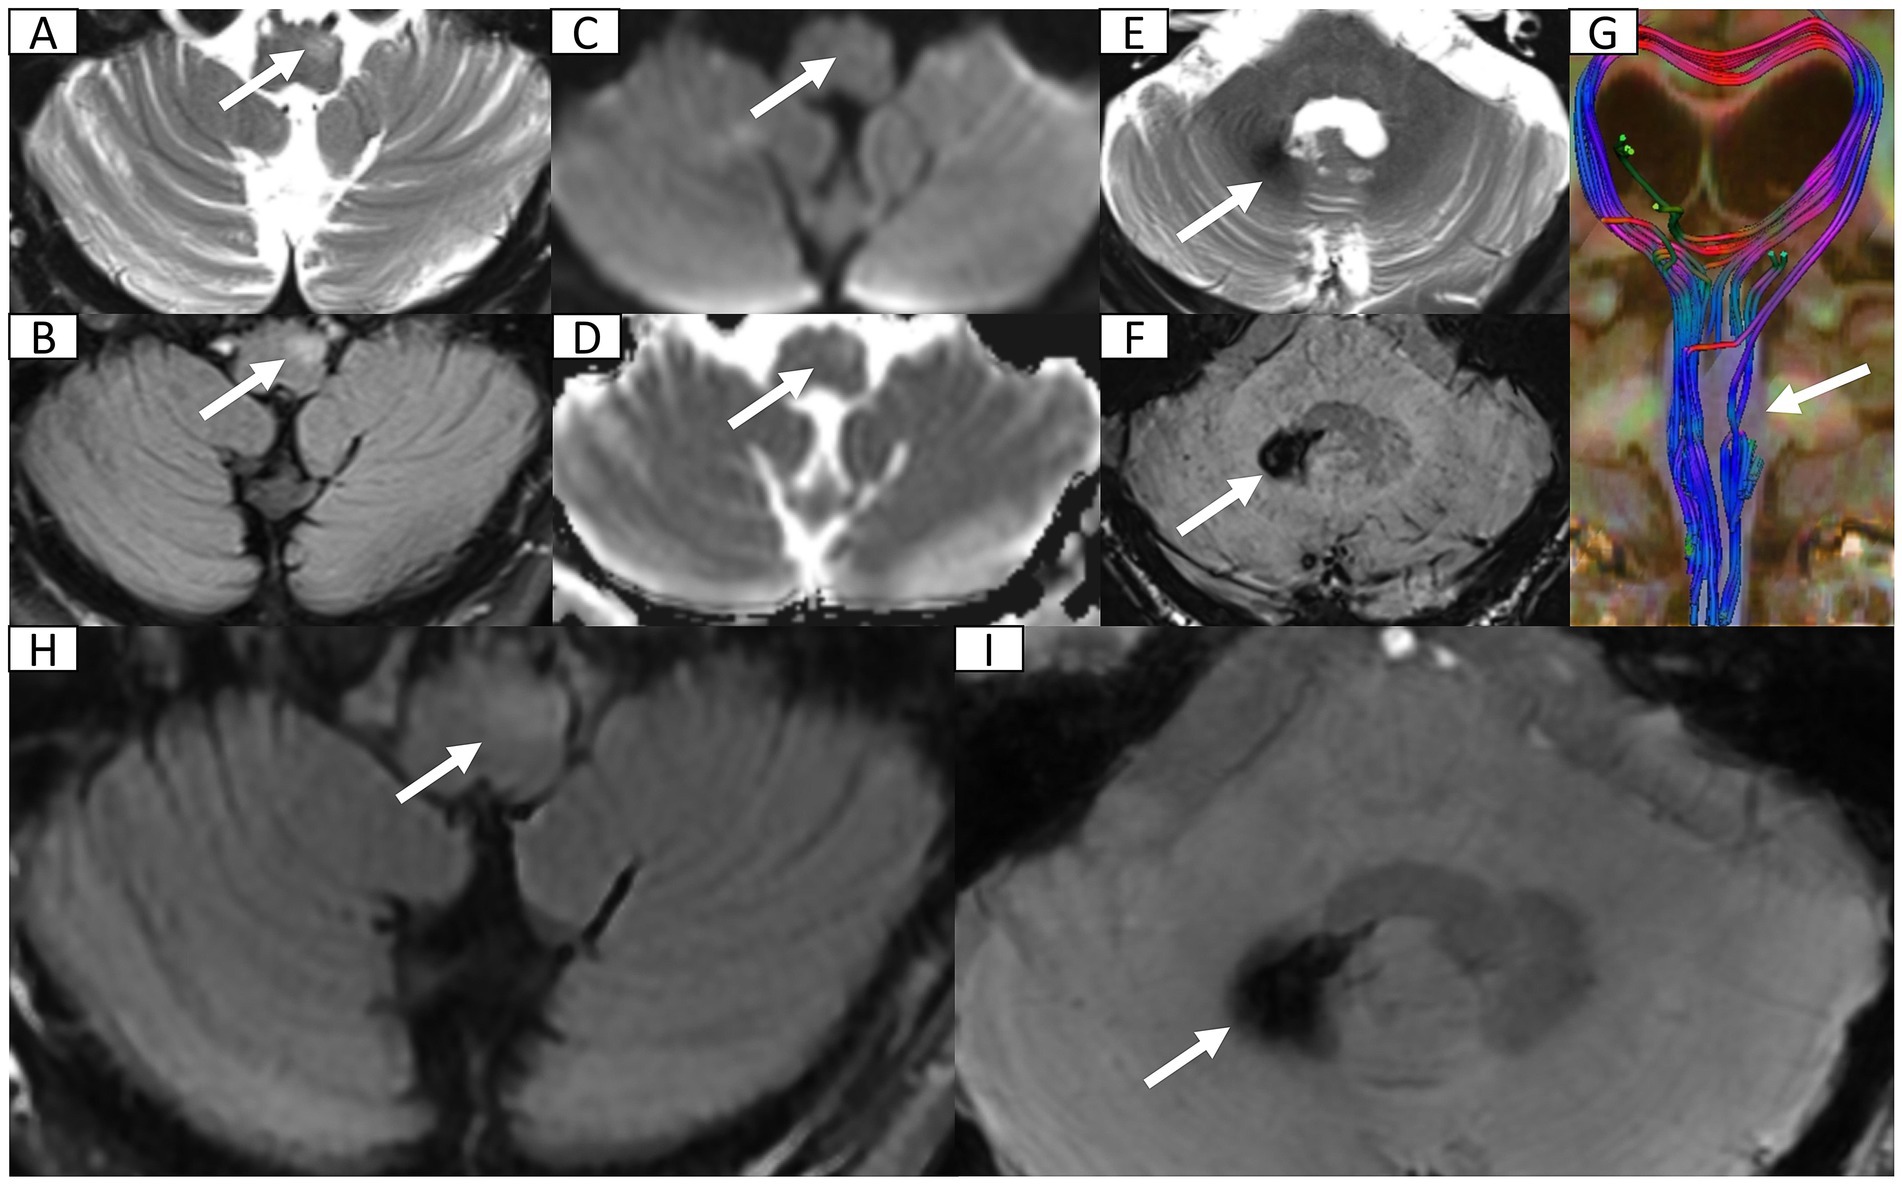

A 72-year-old male with type 2 diabetes and hypertension presented with a 7-day history of fever, headache, and vomiting. Notably, blood glucose was not routinely monitored. Five years prior, he had discontinued smoking and alcohol consumption. Initial head computed tomography (CT) revealed a right cerebellar hematoma with multiple hypodense lesions showing partial rim enhancement (Supplementary Figures S1A–C). CT angiography excluded vascular abnormalities (Supplementary Figure S1D). Upon admission, he was alert with dysarthria, dysphagia, and unsteady gait, but preserved cognition. No prior history of unconsciousness, visual abnormalities, aspiration, seizures, or facial nerve dysfunction. Physical exams showed bilaterally responsive pupils (3 mm), normal muscle strength and tone, and no pathological reflexes. Vital signs revealed fever (38.8 °C) and blood tests showed mild leukocytosis (10.0 × 109/L). Head magnetic resonance imaging (MRI, 1.5 T) with diffusion-weighted imaging (DWI) and contrast enhancement confirmed multiple brain abscesses, hemorrhagic cerebellar lesion, meningitis, and subdural empyema (Figure 1), establishing complicated intracranial infection diagnosis. Management included supportive care [oxygen, intravenous (IV) fluids, expectorants, electrolyte correction, and glycemic and hypertensive control], antiemetics (dolasetron mesylate 12.5 mg IV bid and ondansetron 8 mg IV bid), and antimicrobials (cefoperazone 4 g IV q12h and linezolid 600 mg IV q12h). Symptoms resolved within 7 days. He was discharged with instructions for 1-month follow-up MRI but was lost to follow-up.

Figure 1

Figure 1. Head 1.5 T MRI after first admission. (A,B) Axial T1-weighted imaging (T1WI) and T2-weighted imaging (T2WI) reveal multiple cerebellar nodules and subacute hemorrhage (arrow) in the right cerebellum. (C) Axial fluid-attenuated inversion recovery (FLAIR) sequence demonstrates multiple hyperintense nodules with surrounding vasogenic edema. (D) Post-contrast axial T1WI confirms ring-enhancing abscesses in bilateral cerebellum. (E,F) Axial diffusion weighted imaging and corresponding apparent diffusion coefficient map indicate restricted diffusion within abscess cavities suggestive of viscous purulent content. (G) Post-contrast axial T1WI at the pontine level shows disseminated supratentorial infection including ring-enhancing abscesses in bilateral occipital and right temporal lobes and leptomeningeal enhancement (meningitis). (H) Axial FLAIR sequence demonstrates crescentic hyperintensity along cerebral convexities indicating subdural empyema.